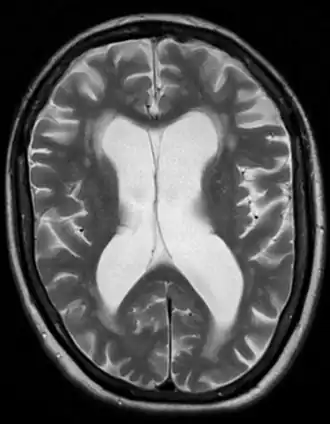

Atrophie cérébrale due à une démence vasculaire